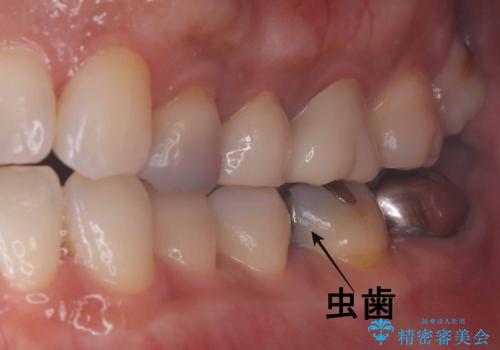

- 銀歯の下の虫歯です。お写真で分かるように広範囲で深い虫歯でした。

1歯はオールセラミッククラウンもう1歯はセラミックインレーで治療を行いました。

かなり虫歯が大きく深かったですが、神経は取らずに残す事が出来ました。